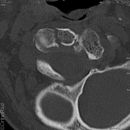

BWK 5 Fraktur